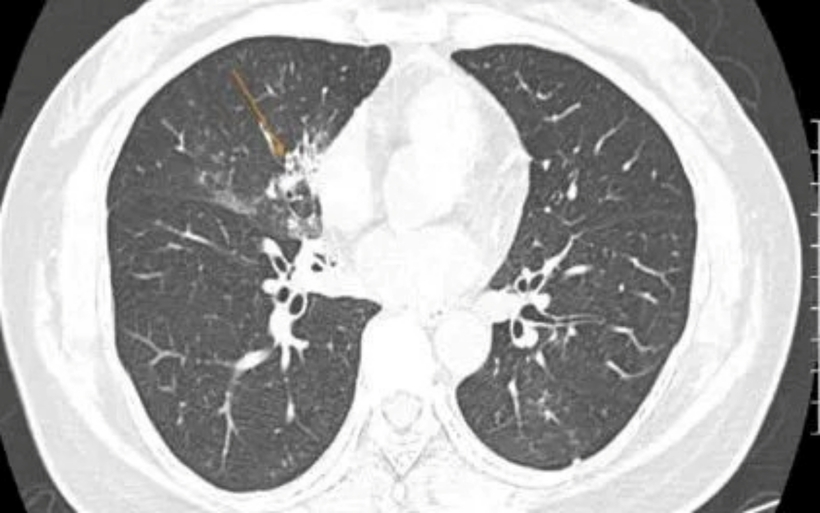

Hình ảnh chụp cắt lớp vi tính cho thấy đám đông đặc kèm kính mờ ở phổi. Ảnh: Thời báo VTV

Hình ảnh CT ngực phát hiện đám đông đặc kèm kính mờ ở thùy giữa phổi phải và thùy dưới phổi trái - tổn thương điển hình của viêm phổi nặng. Đồng thời, xét nghiệm PCR đờm và nuôi cấy vi sinh xác định tác nhân gây bệnh là Streptococcus pneumoniae - phế cầu khuẩn.